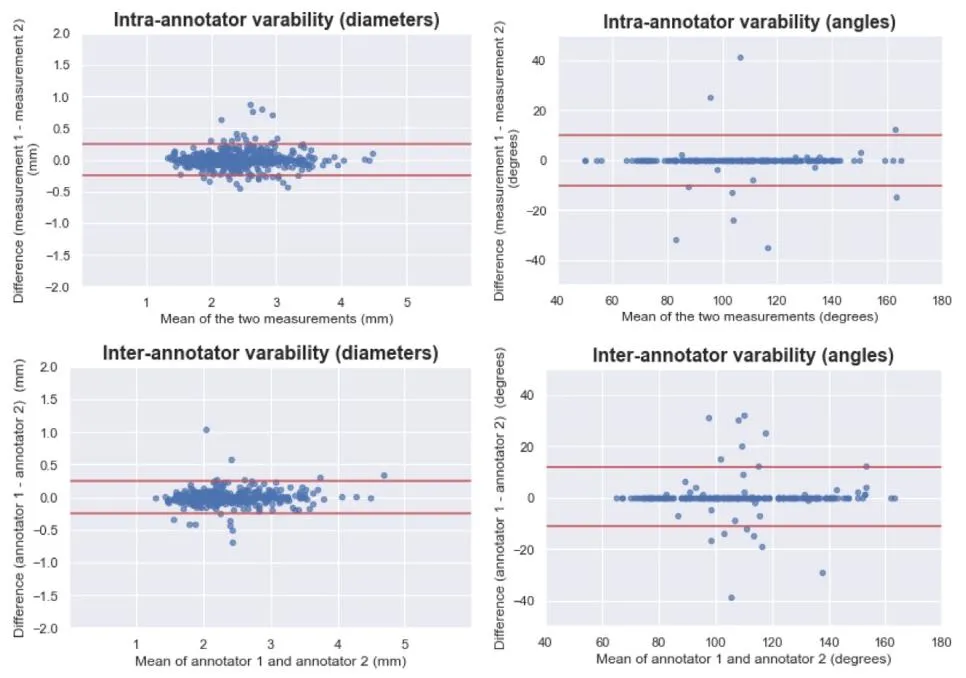

Fig. 5. Bland-Altman plots illustrating the intra- and inter-annotator variability for the artery diameters (left column) and bifurcation angles (right column). The dotted black linesindicate the mean difference, or bias. The red lines show the 95% limits of agreement (LoA). Upper left: bias 0.01 mm, LoA [−0.24 and 0.26 mm]. Lower left: bias <0.01 mm,LoA [−0.24 and 0.24 mm]. Upper right: bias −0.3 degrees, LoA [−10 and 10 degrees]. Lower right: bias 0.2 degrees, LoA [−11 and 12 degrees].

图5. 展示动脉直径(左列)和分叉角度(右列)的标注者内部及标注者间变异性的Bland-Altman图** 黑色虚线表示平均差异(即偏差)。红色线表示95%一致性界限(LoA)。 左上:偏差为0.01毫米,95%一致性界限为[-0.24毫米,0.26毫米]。 左下:偏差小于0.01毫米,95%一致性界限为[-0.24毫米,0.24毫米]。 右上:偏差为-0.3度,95%一致性界限为[-10度,10度]。 右下:偏差为0.2度,95%一致性界限为[-11度,12度]。